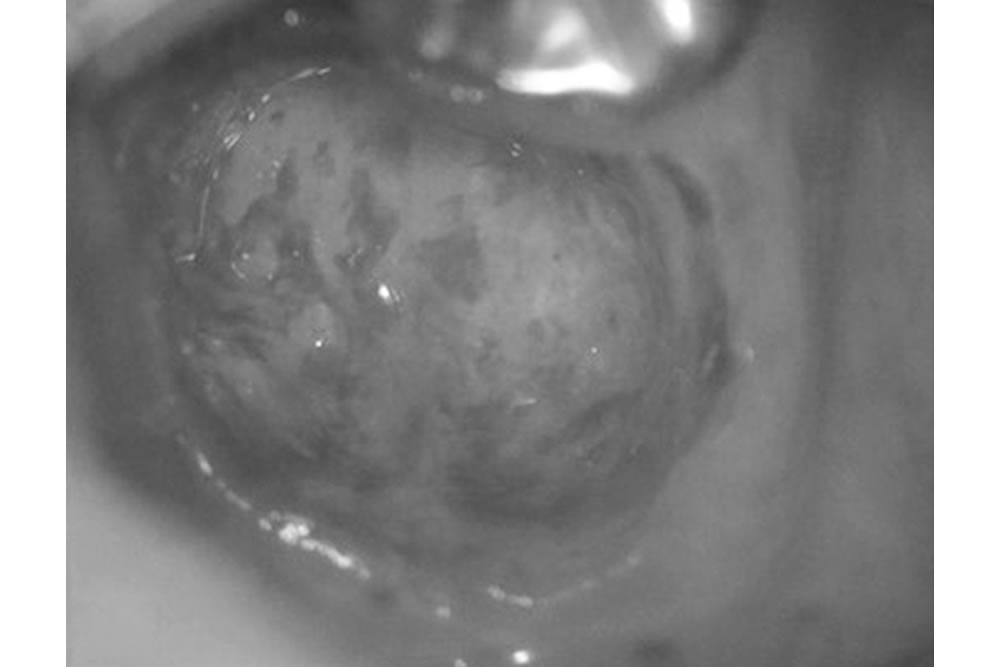

かぶせ物の装着・治療完了

かぶせ物を装着した直後の写真です。歯肉がだいぶきれいで赤味もなく、腫れもほとんどない状態です。歯根が折れていた状況からすると、かなり良好に回復したと言えます。なぜなら、現代医学では歯根破折してしまうと、抜歯するのが常識だからです。

つまり、ここまで回復することは考えられない、というのが通説なのです。ただし、くれぐれも誤解してはいけない点ならびにご理解いただかねばならない点がいくつかあります。

そもそも本症例は、診断上は抜歯となるレベルの状態であり、治療によって歯が100%元の状態に回復することはありません。そのため、術後も多少の違和感が残るなど、何らかの不快症状が生じる可能性があることは、あらかじめご理解いただく必要があります。